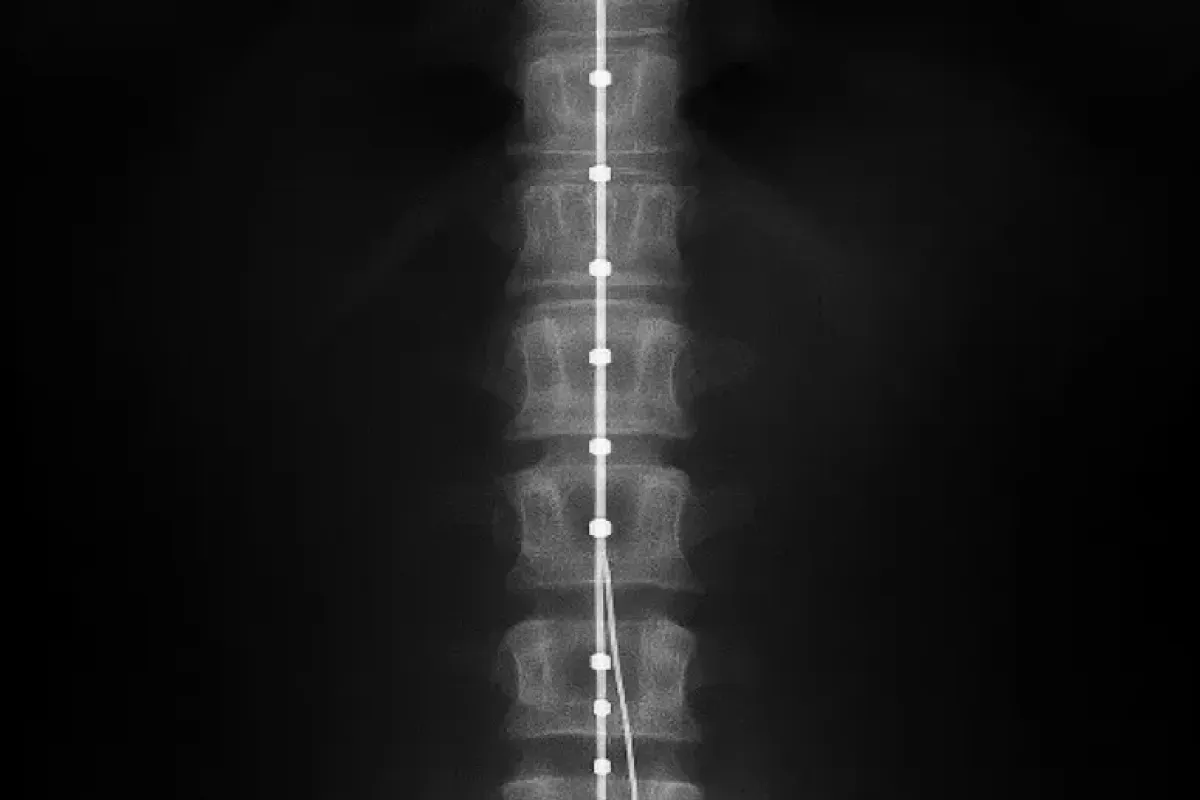

Un cambio di passo nella terapia del dolore arriva da Perugia: all’Azienda ospedaliera Santa Maria della Misericordia sono stati eseguiti i primi impianti di neurostimolatori midollari e periferici presso il Centro di medicina del dolore. Una procedura avanzata, già diffusa nei principali hub europei, che consente di modulare i segnali nervosi responsabili della sofferenza cronica senza ricorrere ai farmaci. Per l’Umbria significa offrire ai pazienti più fragili un’opportunità concreta quando le terapie convenzionali – farmacologiche o chirurgiche – non funzionano più.

Il principio è lo stesso dei pacemaker cardiaci, ma applicato alle vie del dolore: un generatore di impulsi impiantato sottocute invia microcorrenti agli elettrodi posizionati a livello del midollo spinale o in prossimità dei nervi responsabili della trasmissione algica. In questo modo il segnale doloroso viene “riprogrammato” e percepito in maniera attenuata o, in alcuni casi, annullato.

La tecnologia di ultima generazione consente inoltre una regolazione fine, personalizzata in base alla storia clinica del paziente, con protocolli calibrati su intensità, frequenza e pattern di stimolazione. L’obiettivo non è solo ridurre il dolore, ma prevenire l’evoluzione della patologia e restituire autonomia nelle attività quotidiane, con un potenziale impatto positivo anche sul consumo di analgesici e sulla qualità del sonno.